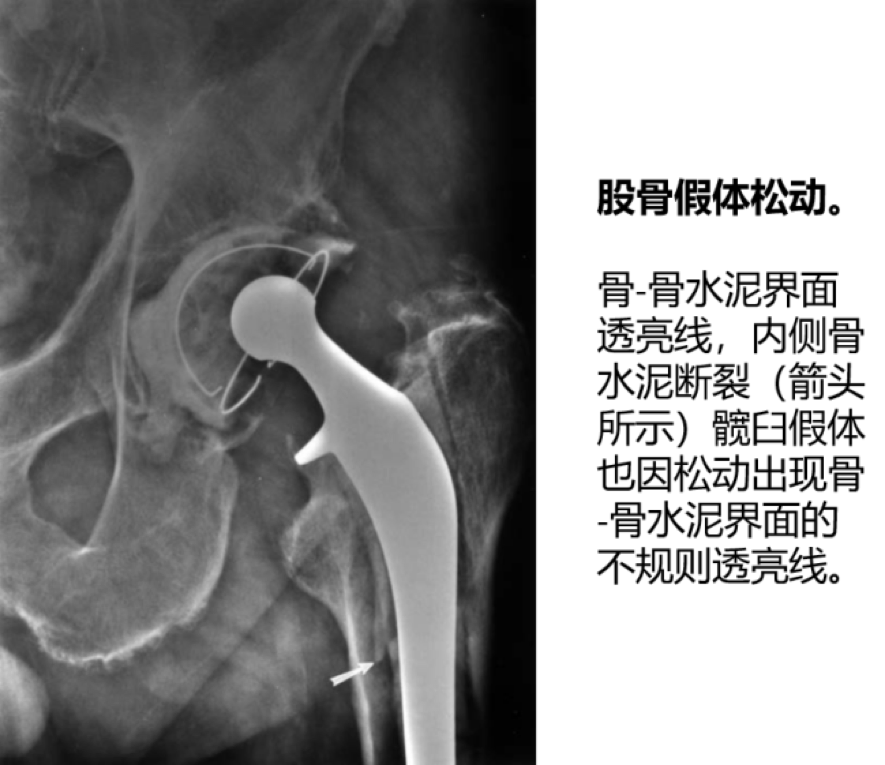

2. 假体无菌性松动:

股骨假体松动发生率为 6%~18%,髋臼假体为 6%~28%。松动是最常见的翻修原因。

影像学特征:

①骨-骨水泥界面/金属-骨水泥界面放射性透亮线大于 2mm;放射性透亮线进行性增宽或不规则;

②股骨假体下沉/移位,髋臼假体移位/内陷;

③假体柄断裂;骨水泥断裂;

④假体表面喷涂材料脱落。